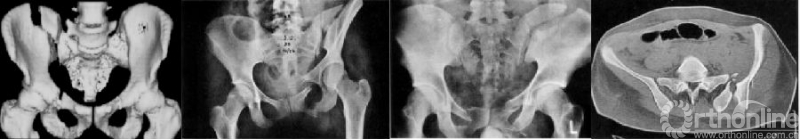

新月形骨折脱位是侧方挤压损伤的一个亚型,大约占骨盆环损伤的12%,为骶髂关节的骨折脱位,因髂后上棘的骨折块呈新月形而得名。因后方的骶髂关节韧带复合体仍然连接到骶骨,故新月形骨折很少伴随危及生命的血流动力学不稳定。

图1 新月形骨折为波及骶髂关节的骨折-脱位,后方的骶髂关节韧带复合体仍然连接到骶骨

图2 新月形骨折波及骶髂关节的范围有明显的的异质性(图1-4为不同类型的新月形骨折脱位)